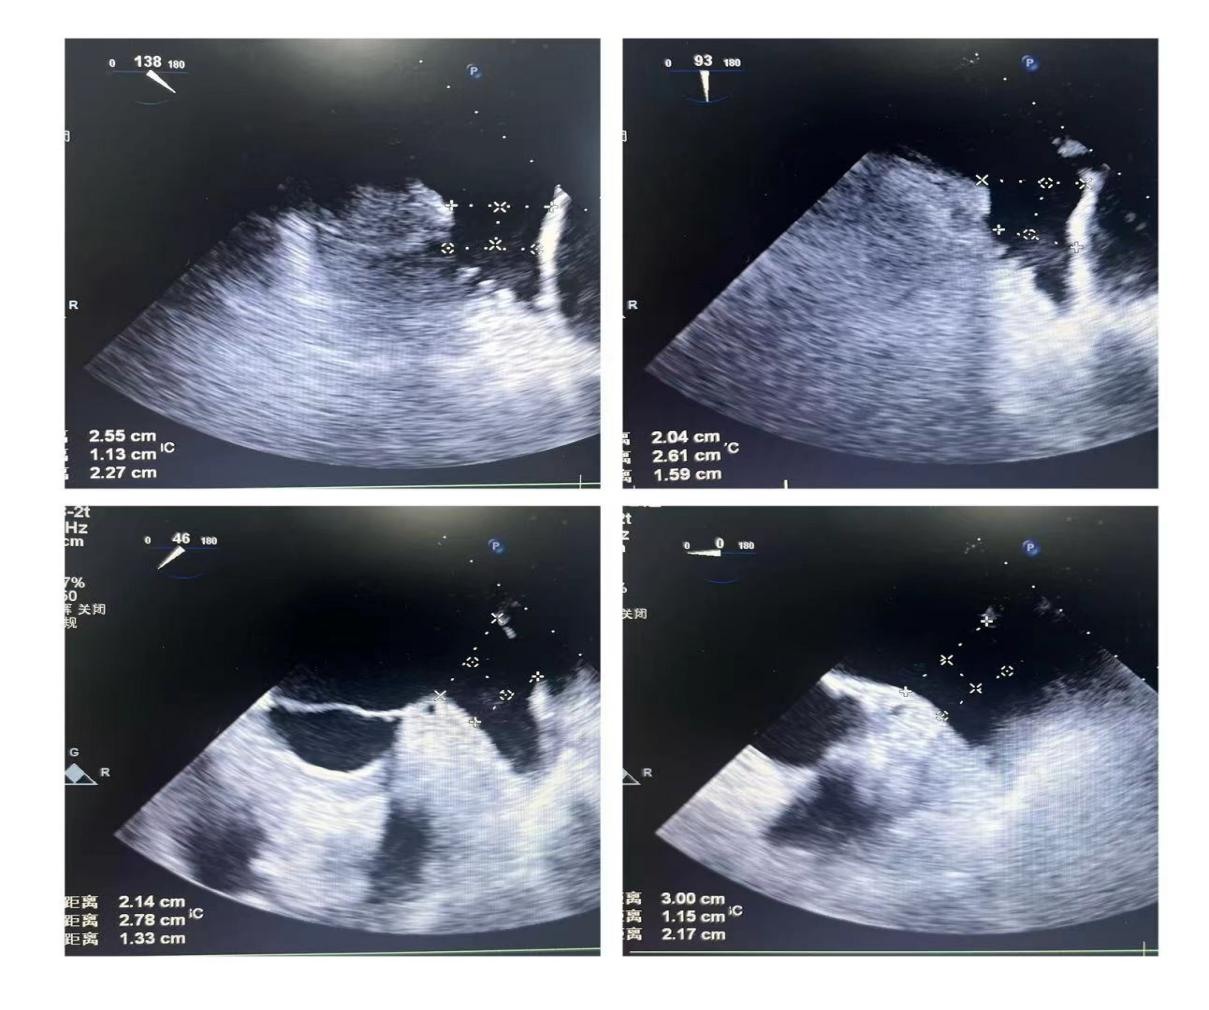

潘教授通过食道超声从4个不同的角度来观察患者左心耳的形态情况,显示心耳为反鸡翅型,位置较低,锚定区为23mm,封堵区为26mm。术者结合多年的临床经验,最终选用型号为LT-LAA-2632的LAmbre™左心耳封堵器对患者进行封堵。

▲(图:通过超声观察进行穿刺)

在食道超声引导下进行房间隔穿刺,由于心耳为反鸡翅型,穿刺位点需靠下靠前,潘教授先在90度双腔切面将定位靠下,再在45度主动脉短轴切面将定位靠前。穿刺成功后上导丝交换J9集团国际LAnavi™分段控弯导引系统送至心耳口部,经过A、B双弯的调整使得鞘管轴向与心耳同轴,获得理想封堵位置。然后推送钢缆释放出固定盘,锚定后退鞘释放出封堵盘。超声下观察贴合良好,无明显残余分流,牵拉测试稳定,即释放左心耳封堵器。释放后再次通过超声各个角度进行验证,封堵结果完美有效,整个过程一气呵成,手术取得了极大的成功。